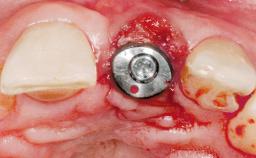

Late Placement of an Implant in a Maxillary Left Central Incisor Site

Type of Implants One-Piece|Reduced-Diameter

Attachment One-Piece|Reduced-Diameter

Soft Tissue Grafting Simultaneous